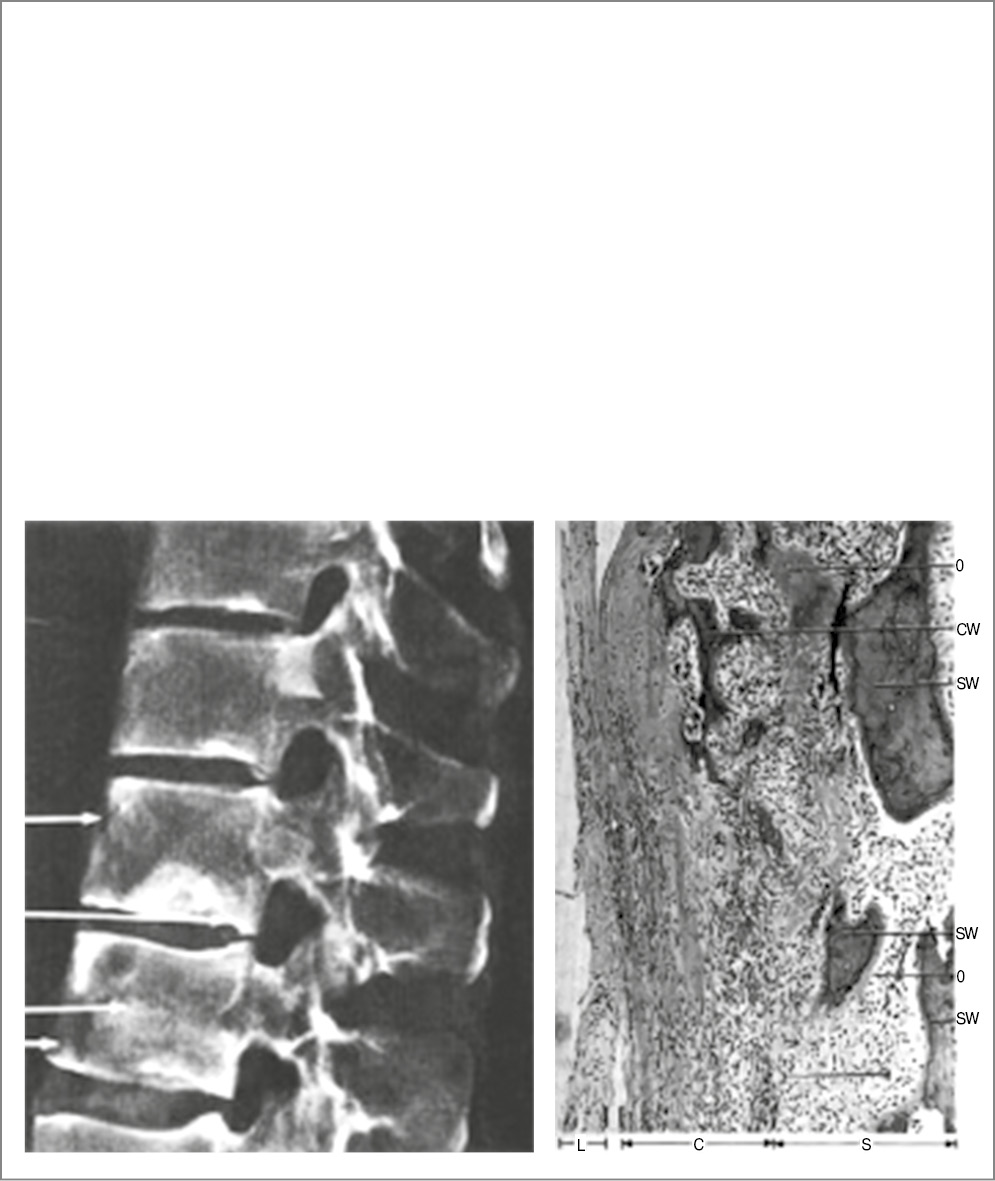

Впервые наглядно продемонстрировать морфогенез переднего спондилита удалось швейцарскому врачу M. Aufdermaur на секции 25-летнего пациента с АС длительностью 8 лет. Фотографии из данной статьи приведены на рис. 3 [2].

Рис. 3. Пациент с АС, длительность болезни – 8 лет. Слева на посмертной рентгенограмме в ThXI–ThXII видны признаки переднего спондилита: «лоснящиеся» передние углы, эрозии по передней поверхности тел (верхняя, нижняя стрелки), справа – микроскопическая картина той части позвонка, которая указана на рентгенограмме верхней стрелкой. Отмечается инфильтрация костной ткани воспалительными клетками. L – передняя продольная связка (не изменена), C – кортикальный слой, S – губчатая кость, O – остеоид, CW – фрагмент волокнистой кости, SW – фрагмент волокнистой кости [2].